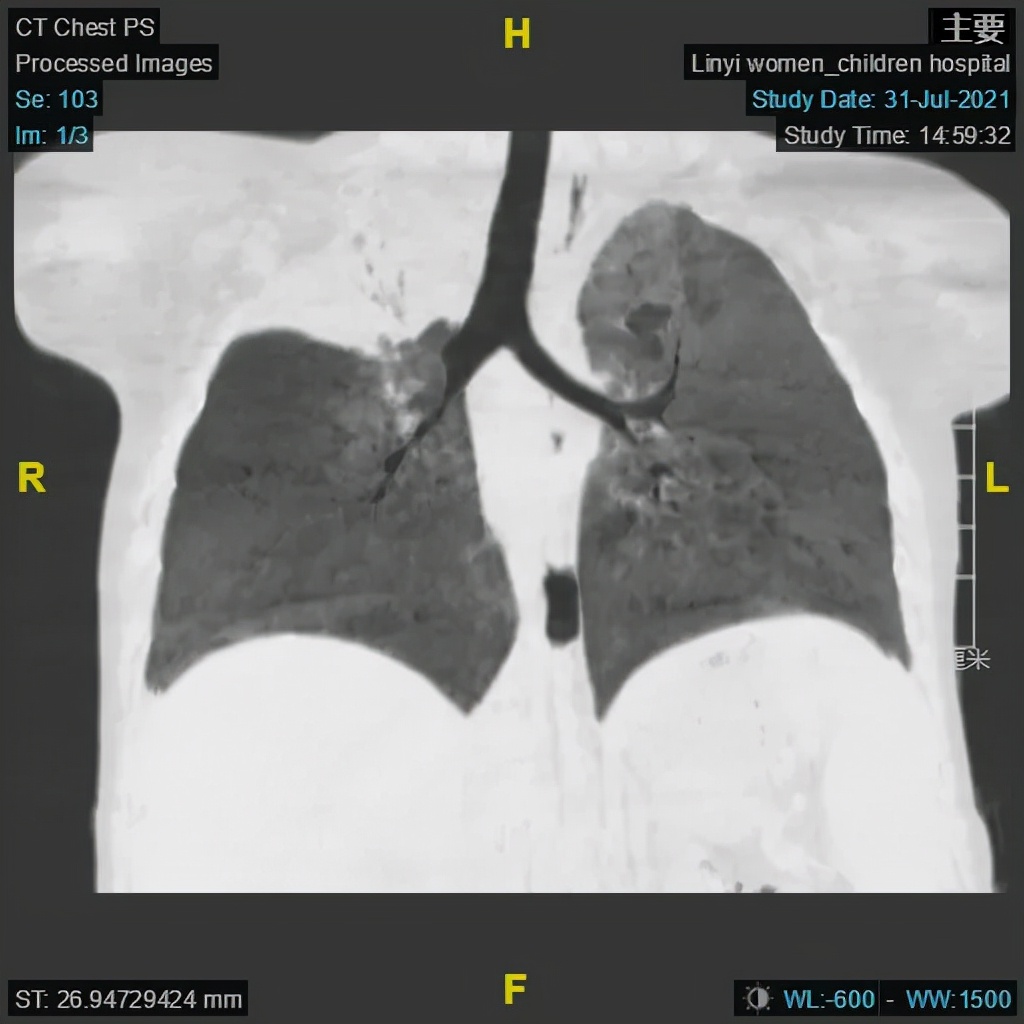

大叶性肺炎术前及术后CT对比图

(电子支气管镜、支气管肺泡灌洗术术前)